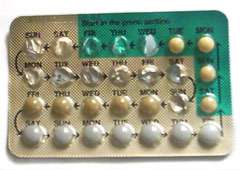

The menstrual cycle is governed by hormonal changes.[6] These changes can be altered by using hormonal birth control to prevent pregnancy.[9] Each cycle can be divided into three phases based on events in the ovary (ovarian cycle) or in the uterus (uterine cycle).[1] The ovarian cycle consists of the follicular phase, ovulation, and luteal phase whereas the uterine cycle is divided into menstruation, proliferative phase, and secretory phase.

While some forms of birth control do not affect the menstrual cycle, hormonal contraceptives work by disrupting it. Progestogen negative feedback decreases the pulse frequency of gonadotropin-releasing hormone (GnRH) release by the hypothalamus, which decreases the release of follicle-stimulating hormone (FSH) and luteinizing hormone (LH) by the anterior pituitary. Decreased levels of FSH inhibit follicular development, preventing an increase in estradiol levels. Progestogen negative feedback and the lack of estrogen positive feedback on LH release prevent a mid-cycle LH surge. Inhibition of follicular development and the absence of a LH surge prevent ovulation.[86][87][88]

The degree of ovulation suppression in progestogen-only contraceptives depends on the progestogen activity and dose. Low dose progestogen-only contraceptives—traditional progestogen only pills, subdermal implants Norplant and Jadelle, and intrauterine system Mirena—inhibit ovulation in about 50% of cycles and rely mainly on other effects, such as thickening of cervical mucus, for their contraceptive effectiveness.[89] Intermediate dose progestogen-only contraceptives—the progestogen-only pill Cerazette and the subdermal implant Nexplanon—allow some follicular development but more consistently inhibit ovulation in 97–99% of cycles. The same cervical mucus changes occur as with very low-dose progestogens. High-dose, progestogen-only contraceptives—the injectables Depo-Provera and Noristerat—completely inhibit follicular development and ovulation.[89]

Combined hormonal contraceptives include both an estrogen and a progestogen. Estrogen negative feedback on the anterior pituitary greatly decreases the release of FSH, which makes combined hormonal contraceptives more effective at inhibiting follicular development and preventing ovulation. Estrogen also reduces the incidence of irregular breakthrough bleeding.[86][87][88] Several combined hormonal contraceptives—the pill, NuvaRing, and the contraceptive patch—are usually used in a way that causes regular withdrawal bleeding. In a normal cycle, menstruation occurs when estrogen and progesterone levels drop rapidly.[85] Temporarily discontinuing use of combined hormonal contraceptives (a placebo week, not using patch or ring for a week) has a similar effect of causing the uterine lining to shed. If withdrawal bleeding is not desired, combined hormonal contraceptives may be taken continuously, although this increases the risk of breakthrough bleeding.